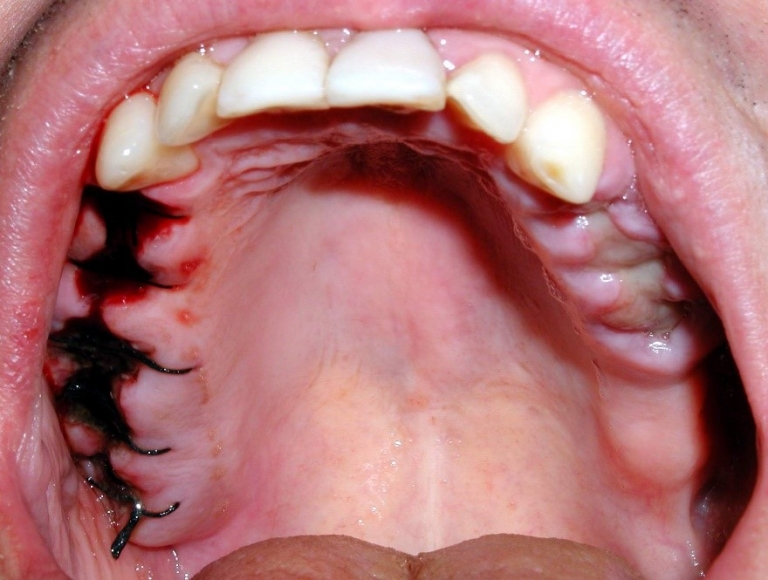

Removing Tooth Extraction Stitches . Dissolvable stitches are used after tooth extraction, such as wisdom tooth removal, to tack the gum tissue flap back into its original place. The stitches will dissolve by themselves within a week to 10 days, so you. The stitches will dissolve in approx. If the stitches are present after this time, gently rub them with some toothpaste and this will. You may have stitches, depending on which tooth was removed, and why. Stitches stitches dissolve in 7 to 10 days. It takes up to 2 weeks for the stitches. Stitches if any stitches (sutures) have been used to close the sockets, these stitches will be dissolvable unless you are told otherwise by ward staff. If you have stitches, these usually dissolve and you do not need to have them removed. What is involved in removing a tooth? Usually tooth removal is straightforward and takes a few minutes.

Stitches stitches dissolve in 7 to 10 days. The stitches will dissolve by themselves within a week to 10 days, so you. The stitches will dissolve in approx. You may have stitches, depending on which tooth was removed, and why. If the stitches are present after this time, gently rub them with some toothpaste and this will. If you have stitches, these usually dissolve and you do not need to have them removed. Usually tooth removal is straightforward and takes a few minutes. It takes up to 2 weeks for the stitches. Stitches if any stitches (sutures) have been used to close the sockets, these stitches will be dissolvable unless you are told otherwise by ward staff. Dissolvable stitches are used after tooth extraction, such as wisdom tooth removal, to tack the gum tissue flap back into its original place.